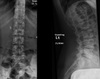

What distinctive vertebral body appearance is noted?

H-shaped vertebrae (DDx: Sickle cell anemia, thalassemia)

39

Give 2 differentials in order of likelihood.

1. Sickle cell anemia 2. Thalassemia